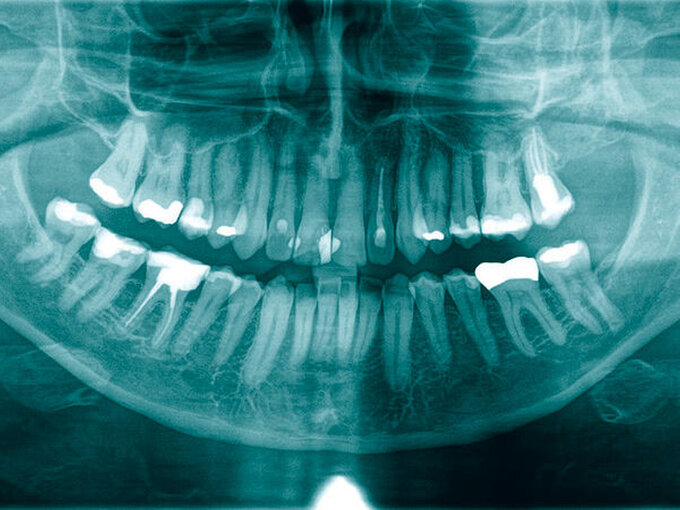

Aus diesem Grund wurde bereits nach der ersten klinischen Befundaufnahme ein Notfall-CT mit Kontrastmittel angemeldet, ein augenärztliches Konsil gestellt und der diensthabende HNO-Kollege konsiliarisch hinzugezogen. Zwischenzeitlich war ein DVT durchgeführt worden, das einen Wurzelrest 25 als offensichtliche Ursache der odontogenen Sinusitis maxillaris zeigte, die sich zudem auf Siebbein und Stirnhöhle ausgedehnt hatte (Abbildung 4).

Bei der einseitigen Sinusitis maxillaris sollte immer eine odontogene Ursache ausgeschlossen werden. Dabei ist neben der klinischen Untersuchung mit Perkussion und Vitalitätsproben aller Zähne der betroffenen Oberkieferseite eine radiologische Diagnostik notwendig. In der Regel reicht eine Panoramaschichtaufnahme aus. Gelegentlich ist eine Einzelzahndiagnostik mit Zahnfilmaufnahme notwendig. Selten ist eine DVT indiziert.